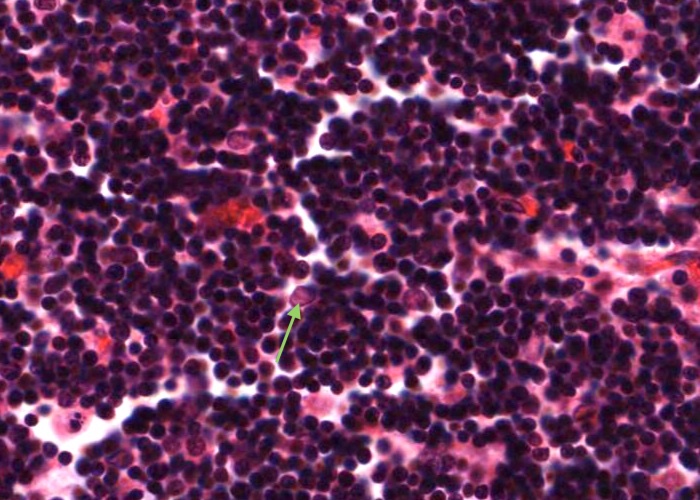

Look at the nodules in the cortex. Identify a germinal centre and the corona (mantle) around it. Most of the cells in the corona are small lymphocytes. In contrast, many of the cells in a germinal centre of the nodule have large, pale nuclei. This is why a germinal centre stains palely.

The maximal magnification is barely adequate. Scan the cortex for a germinal centre in which the cells are not jammed too heavily on top of one another.

If you see a large, pale nucleus which seems to have no cytoplasm at all around it then it is most likely a follicular dendritic cell. These cells actually have a lot of cytoplasm but it is stretched out into long arms that extend out of the plane of section. Their function is to hold antigen molecules on their surface and "present" them to lymphocytes. They are one type of antigen presenting cell. Various other cell types also present foreign or self antigens.

More rarely you will see nuclei as large as those of dendritic cells, but darker and with a discrete rim of basophilic cytoplasm. The cytoplasm will have a sharp outer perimeter. These cells are lymphoblasts. Their edges are visible because they do not have cytoplasmic arms sticking out.

Small lymphocytes dominate the corona. You can also find occasional prolymphocytes, with more, basophilic cytoplasm than small lymphocytes and with larger, paler nuclei. The supporting reticular cells have elongate nuclei. You also may come across a plasma cell or two.

Finally there are substantial numbers of small lymphocytes each with a circular, dark-stained nucleus.